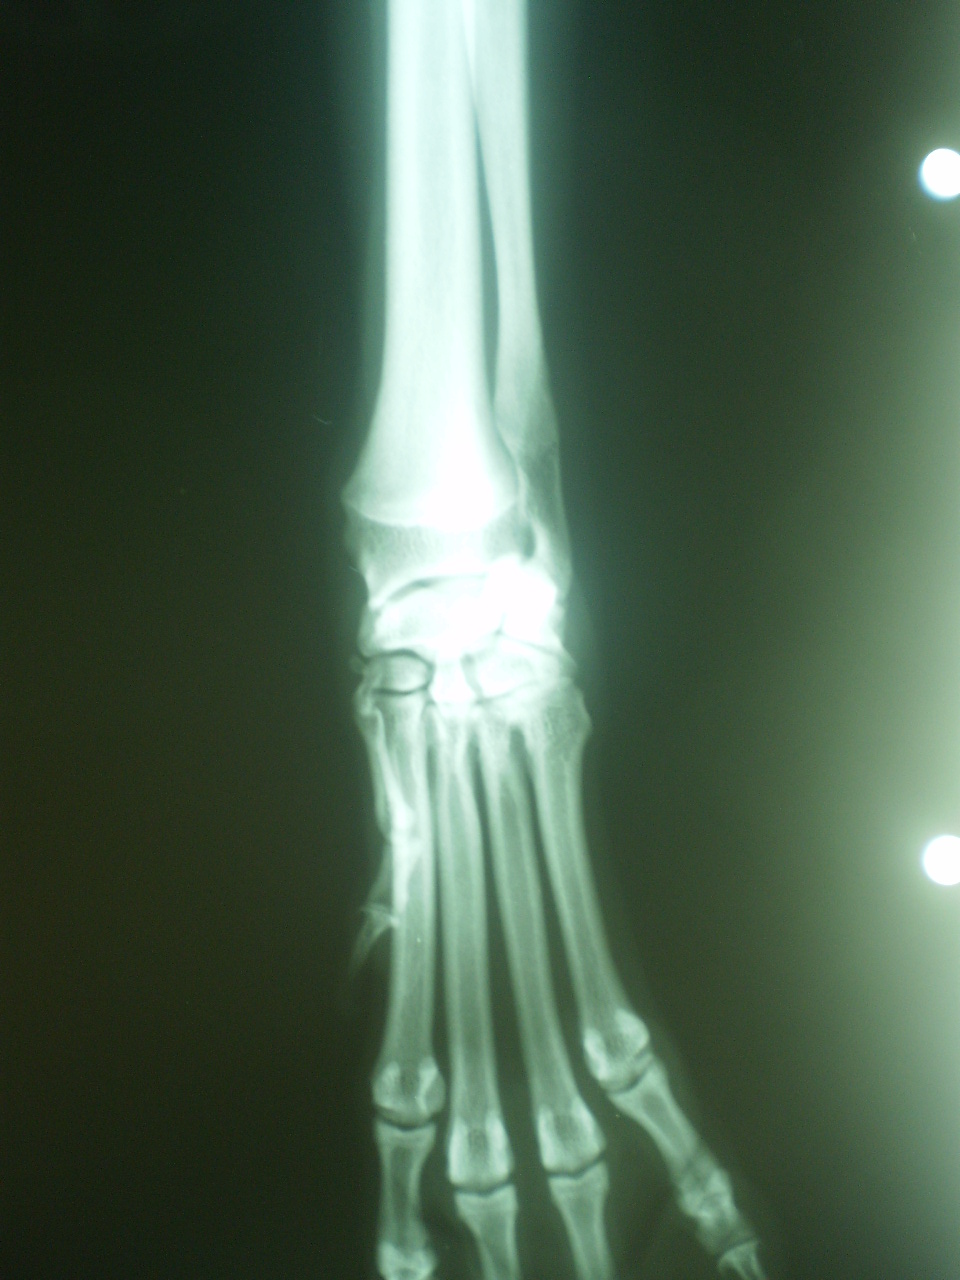

Este es el caso de un perro de raza bodeguero 8 meses de edad, que hace 1 mes sufrio un accidente, atropellado por un tractor. Esto no le supuso mas que una cjera de la EAD que remitió con tratamiento antiinflamatorio sin mayor problema.

Al cabo de las 4-5 semanas la cojera reaparece y realizan estudio radiologico de la extremidad.

Para ver una comparacion, la imagen superior es la imagen de la extremidad opuesta

Bien. daremos respuesta al caso. Hay un dato fundamental que creo que algunos no han tenido en cuenta. El atropello del animal unas semanas anteriores, provoca una lesion a nivel del cartilago de crecimiento dstal del radio. Esas son las fracturas Salter Harris tipo V que provocan el cierre de la linea de creciiento a ese nivel pero no afectan al crecimiento en otras zonas.

En este caso es el radio el que ha cesado su crecimiento produciendo lo conocido como sindrome de radio corto.

El cubito continua su crecimiento formandose finalmente una incongruencia articular tanto a nivel del codo como del carpo.

En el caso que nos ocupa podemos ver en la rx de ambas extremidades el acortamiento de la afectada que ya ronda el 10% de la longitud total de la sana.